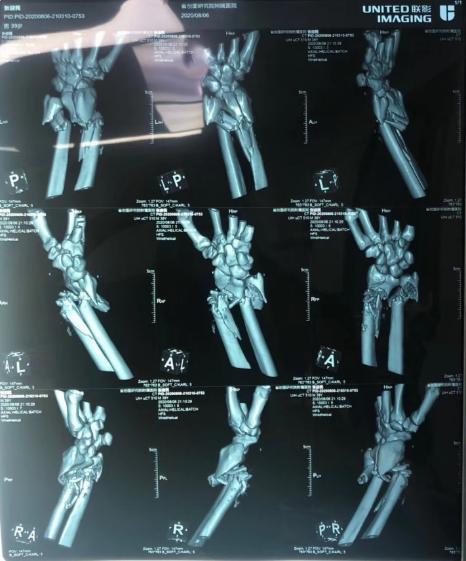

根据安徽省创面与显微外科技术研究院附属中医骨伤医院外一科主任戴文凯回忆:晚上9点多左右,患者是霍邱那边铁矿的,属于机器重压伤,整个前臂中段到腕关节这个位置,整个大约有10公分左右,骨质的粉碎性缺损,皮肤的缺损,神经的缺损,肌腱的缺损和血管的缺损。来的时候已经有六七个小时了,合肥去了几家医院,都说要截肢,厂里没有放弃,到我们医院最后看一下。

来的时候患者再植的意愿比较强烈,查体后发现虽然中间这段毁损比较严重,但远端手腕还是比较完整的,条件还是可以的,所以我们也是制定了方案,骨质的临时固定,神经肌腱先接好,血管缺损后我们从小腿上取相同的静脉血管来补缺损的血管。

一小时,两小时,三小时……伤口清创,清除损毁的肌肉,找到血管、神经、肌腱的断端,将离断的手臂固定,在显微镜下完成血管的移植,进行血运的再通……经过漫长的八小时,手术终于顺利结束。